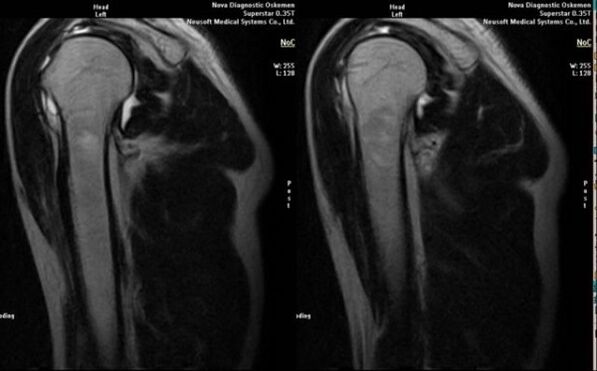

El principal método de diagnóstico para detectar la osteoartritis deformante de la articulación del hombro es la radiografía simple.

- Radiografía de la articulación afectada;

- resonancia magnética y tomografía computarizada;

Los signos que indican directamente el desarrollo de artrosis incluyen la aparición de un estrechamiento significativo del espacio articular, esclerosis de las estructuras subcartilaginosas, adelgazamiento de la propia capa de condrocitos, aparición de osteofitos y depósito de cristales de sal en el líquido intraarticular.